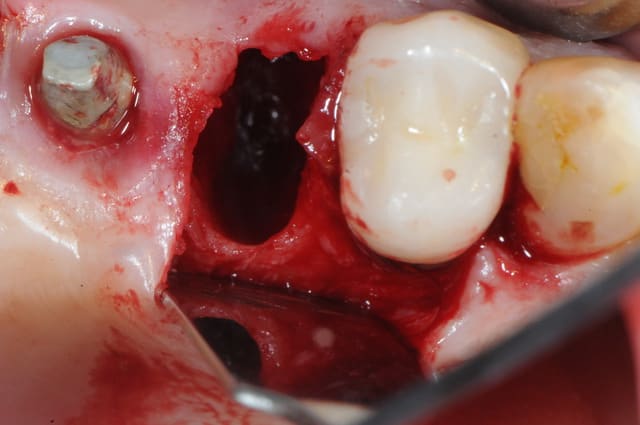

4-5: eh ben oui, elle est détruite! une simple curette insérée dans l'alvéole permet de visualiser l'importance de la perte osseuse vestibulaire.

que faire ??

1- curette en appuie sur la face vestibulaire montrant la destruction osseuse.

2- lambeau pleine épaisseur en palatin pour aller chercher un bout de conjonctif qui soit pédiculé.

3 je décole à partit des rebords de la déhiscence osseuse et reste en contacte permanent avec la corticale osseuse tout en décollant la gencive (elle est soulevé donc)